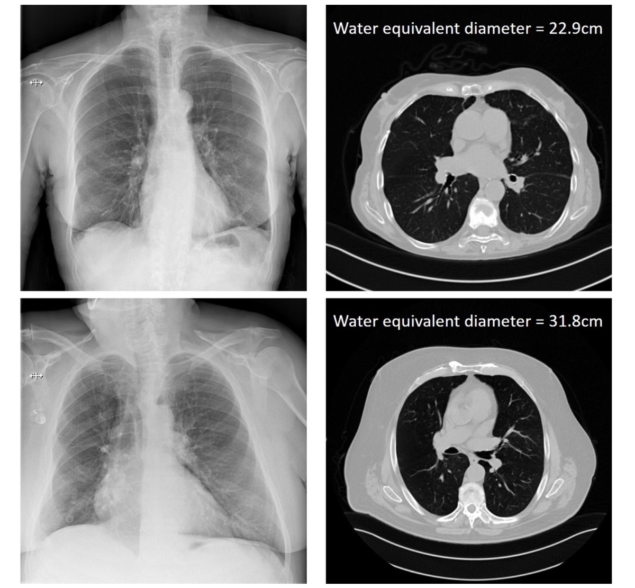

從胸部X光片的DICOM頭信息中計算出的病人的X光衰減,并與CT的黃金標準尺寸測量進行比較。(Courtesy: Hilde Bosmans)

為了建立真實的病人尺寸,研究人員使用CT掃描來計算所有病人的水當量直徑(WED)和水當量厚度(WET)。然后他們將這些真實的WED和WET值與衰減指標的自然對數繪制在胸腔和腹部掃描上。這產生了四條相關曲線,然后可以應用于僅根據投影射線照片的DICOM信息來估計病人的大小。